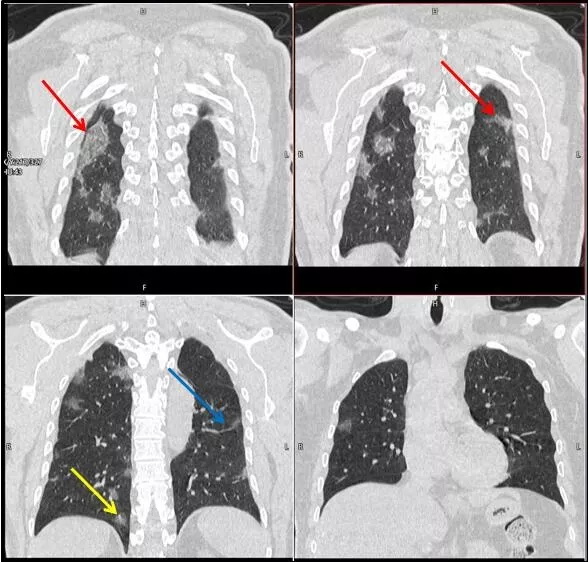

武漢大學中南醫(yī)院影像科副主任張笑春教授發(fā)現(xiàn),目前武漢市家庭聚集性發(fā)病較多,而且大多起病隱匿,一次甚至多次核酸陰性,無任何臨床癥狀,CT檢查卻已顯示為病毒性肺炎特征。

為了盡快篩查新型冠狀病毒肺炎患者,醫(yī)院會選擇影像診斷作為早期發(fā)現(xiàn)新型冠狀病毒感染的肺炎的重要一環(huán)。

CT為當前首選篩查與診斷的主要影像學手段,胸部CT的病毒性肺炎檢出率高。

方舟CT(CT Ark)可以滿足全面的臨床功能,配置16層、32層、64層、128層CT,實現(xiàn)了低劑量掃描要求,配合NDI微劑量迭代技術,智能毫安調控技術,使各種場合下、各部位低劑量掃描得以實現(xiàn);超高分辨率CT病灶靶掃描,使病灶的密度顯示更加精確,能夠顯示病灶內輕度的密度變化,有利于小病灶的密度定量分析和及時診斷。